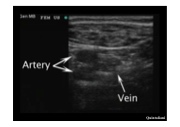

AV